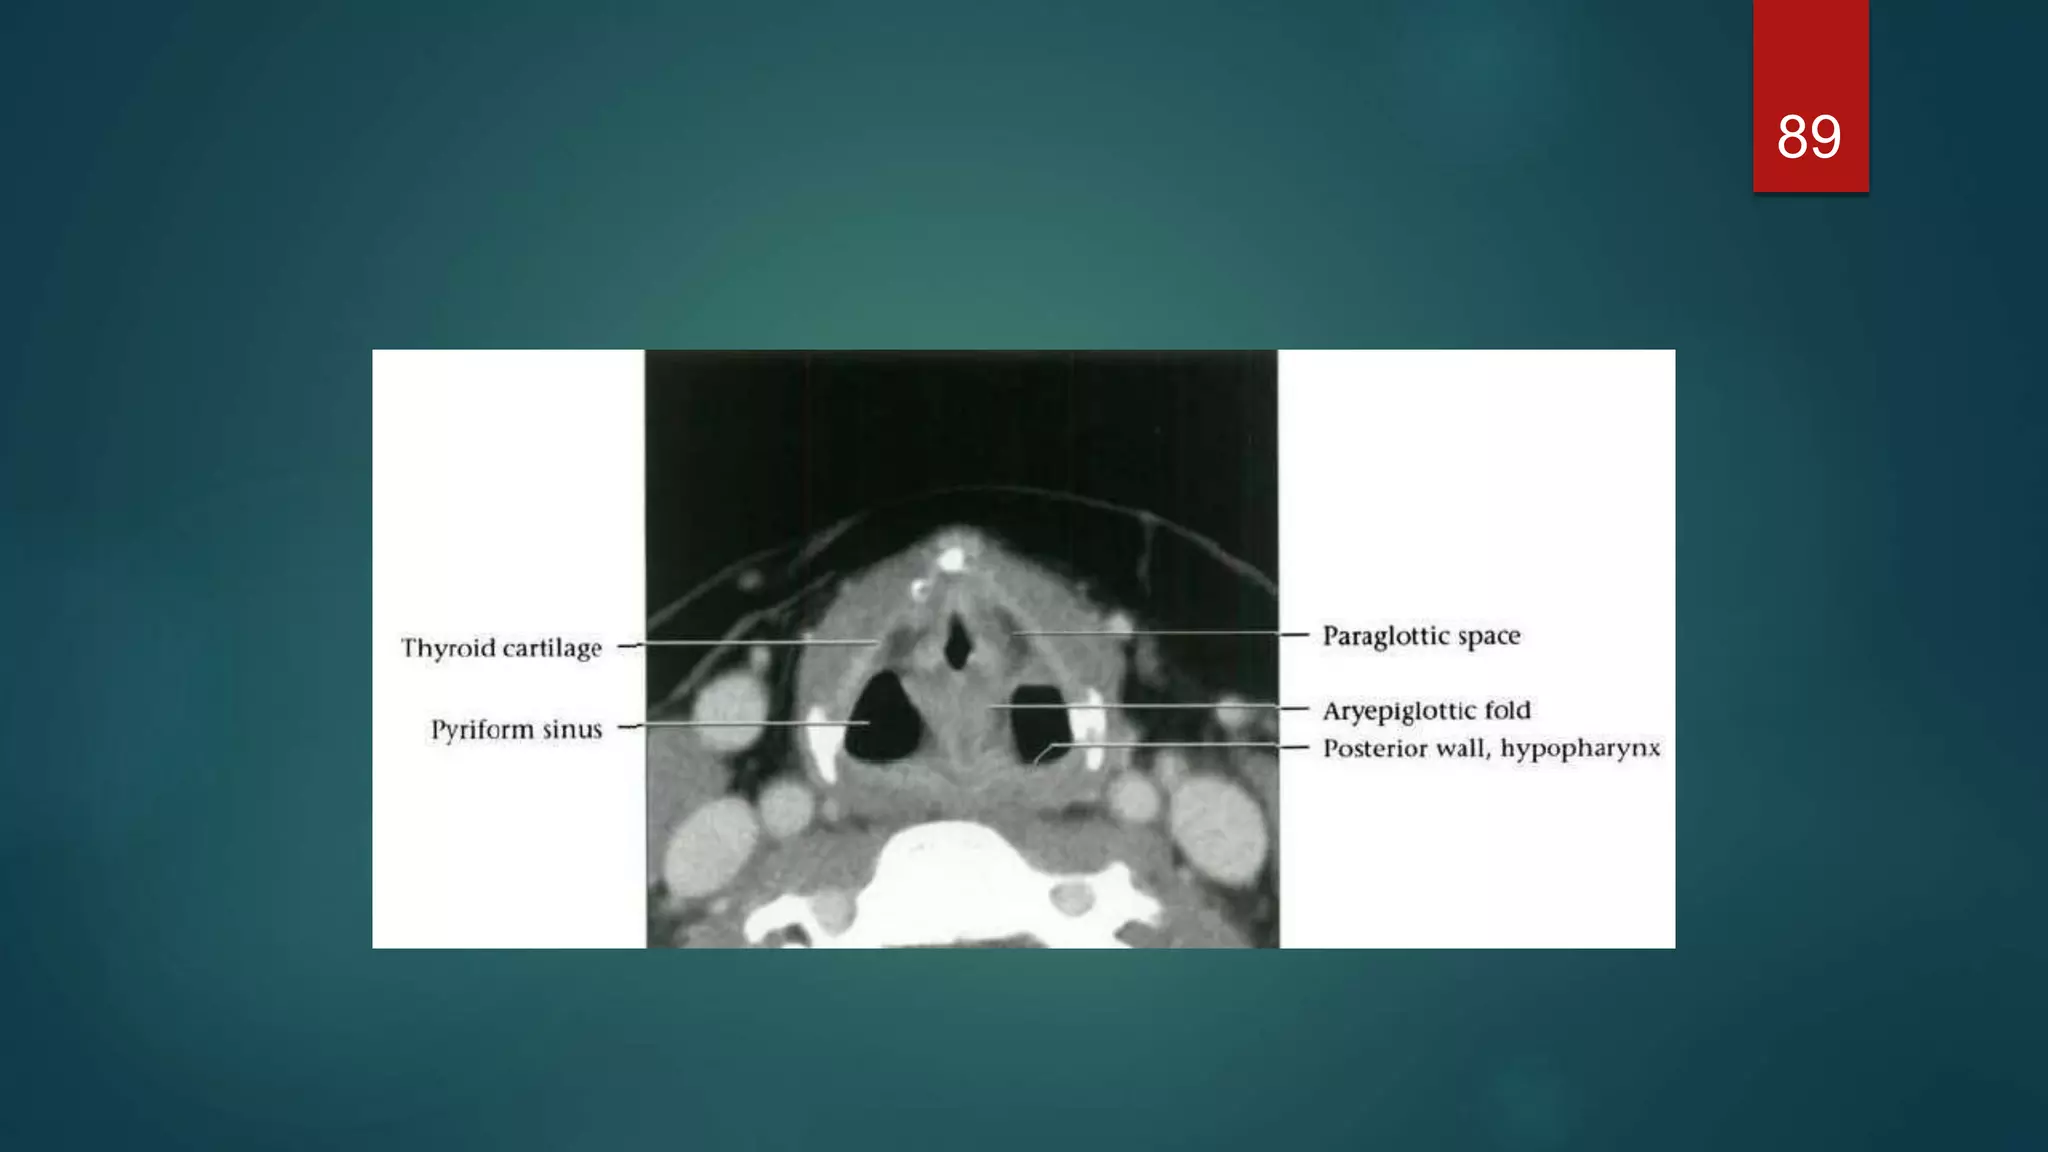

Cross-sectional anatomy of the

larynx

Supraglottic level

 The larynx is anterior to the piriform

sinuses, separated from them by the

aryepiglottic folds.

Cross-sectional anatomy ofthe larynx Supraglottic level  The larynx is anterior to the piriform sinuses, separated from them by the aryepiglottic folds. 71